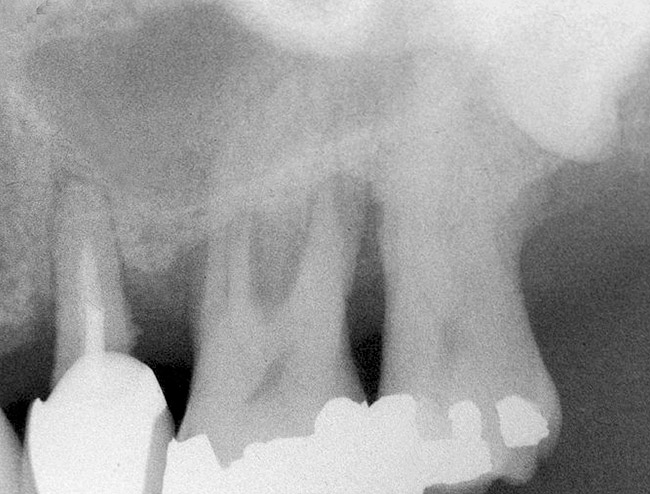

Sinus Floor Elevation in a Socket

The sinus floor elevation technique can be used when a tooth is extracted and there is not enough bone height to support an immediate implant (Figure 8, Figure 9 and Figure 10, Figure 11).32

Figure 8  At site No. 13 the second bicuspid had a hopeless prognosis; it was to be extracted and replaced with an implant after a transcrestal sinus floor elevation.

Figure 8

Figure 9: After the extraction, a 2.1-mm twist drill was used to drill within 1 mm of the subantral floor. A guide pin was placed and a radiograph was taken to ascertain if the drill stopped within 1 mm of the subantral floor.

Figure 9